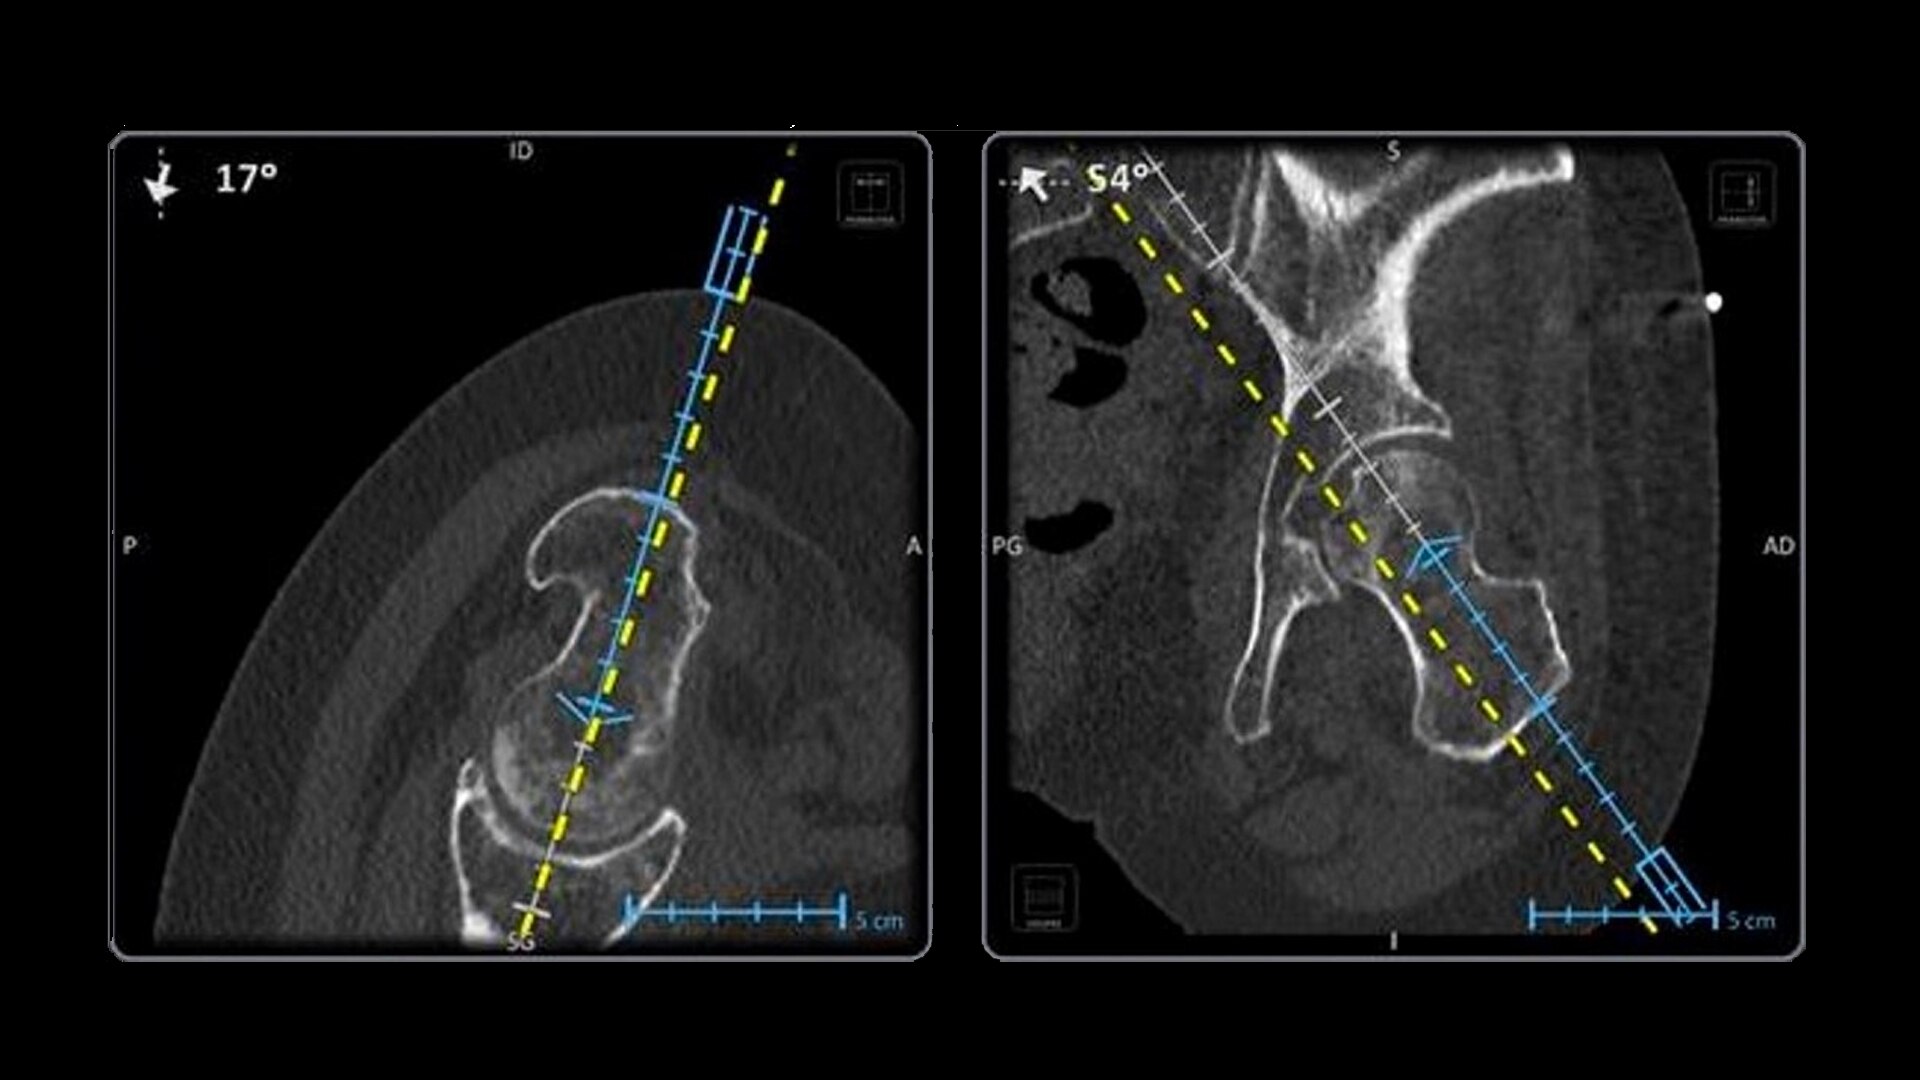

Imactis® CT-Navigation™ is an electromagnetic (EM) navigation solution for CT-guided percutaneous procedures

Imactis® CT-Navigation™ is designed to radically improve efficiency of Interventional procedures for clinicians and hospitals by increasing their accuracy.